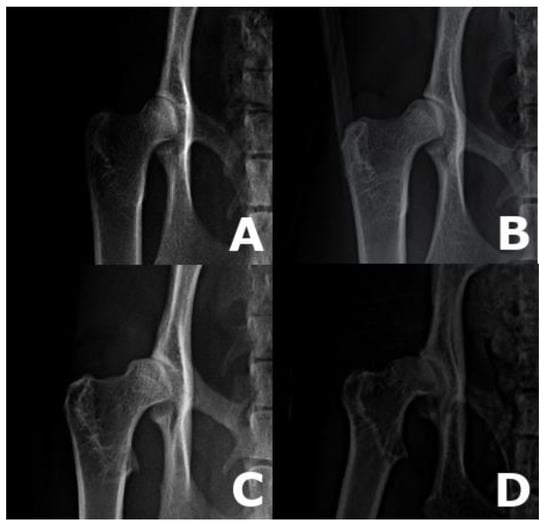

2. Materials and Methods